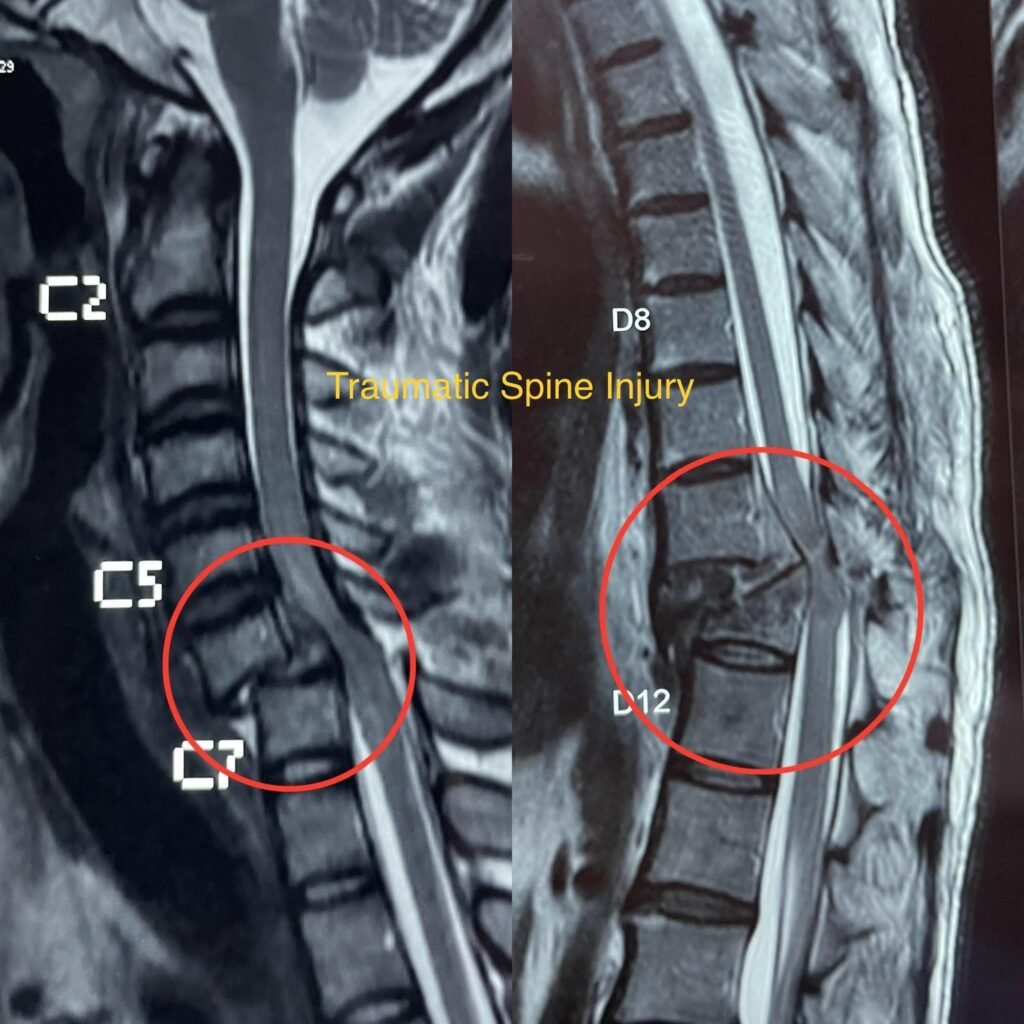

Traumatic Spine Injury

Traumatic Spine Injury refers to damage to the spinal cord, vertebrae, or surrounding tissues caused by trauma, such as motor vehicle accidents, falls, sports injuries, or acts of violence. These injuries can range from mild strains or sprains to severe fractures or dislocations, and they can result in various degrees of neurological deficits.

• Diagnosis typically involves a thorough physical examination, medical history, and imaging studies such as X-rays, CT scans, or MRI to evaluate the extent and severity of the injury.